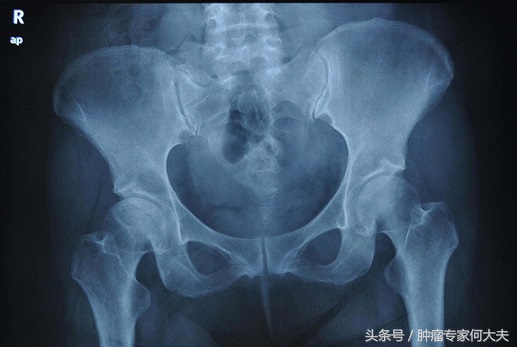

祸不单行,福不双至。龚玥娥万万没想到,有比强直性脊柱炎更大的麻烦降临,半年前,她因为不明原因的非月经期阴道出血,在当地医院妇科检查,高度怀疑宫颈癌,考虑到她有强脊病史,医生不敢轻易诊治,建议她去北京协和医院诊治。在协和医院,32岁的龚玥娥被确诊为宫颈癌晚期,盆腔转移,双侧输尿管受阻,考虑她长时间大量使用激素,骨质疏松,不建议她放化疗,也没有手术指征,只能保守支持治疗。现在她的腹痛越来越厉害,远远超出当年强制性脊柱炎造成的腰腿疼。看到她失落无助的眼神,医生能做的事只能是减轻痛苦,对她来说,现在的问题不再是“不死的癌症”了,而是遭遇着即将不久要死的癌症。只能希望她痛苦少点。

宫颈癌是女性最常见的生殖系统恶性肿瘤。子宫颈,上连子宫,下接阴道,宫颈癌病因被认为与感染HPV病毒有关,大多数宫颈癌病理学类型属于鳞癌,宫颈癌多发于30~40岁中年妇女,但是近年来有低龄化趋向。宫颈病变是中青年女性性与生殖的瓶颈,宫颈癌变更要威胁到其健康与生命。晚期宫颈癌目前缺乏有效治疗办法。